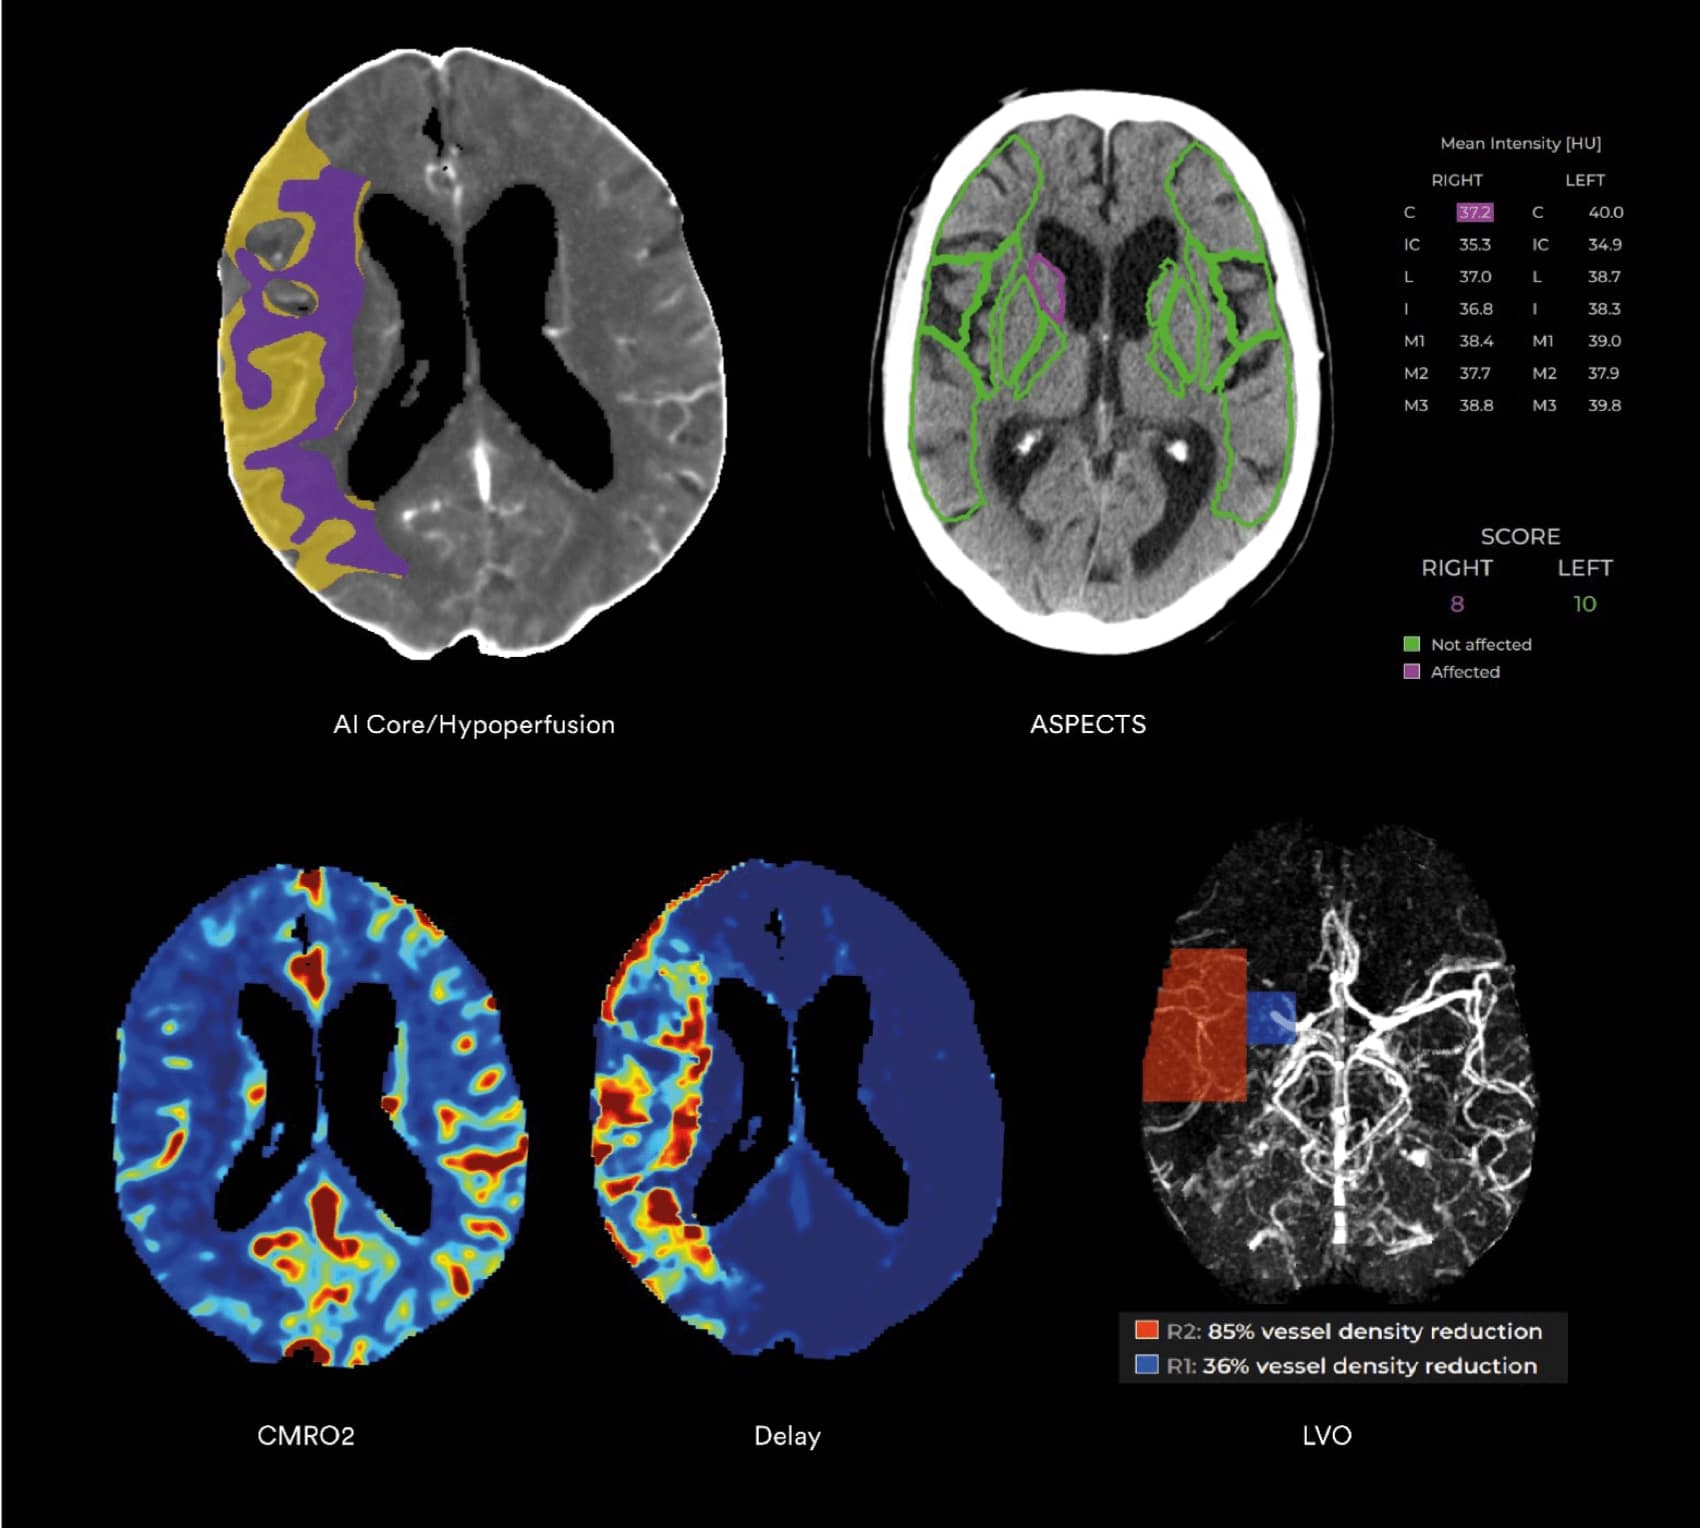

AREA STROKE – Diagnosi avanzata dell’Ictus

- Necessità di una stima accurata del nucleo ischemico e dell’area ipoperfusa.

- Difficoltà nella quantificazione automatica e affidabile delle lesioni.

- Complessità dei protocolli TC/RM in pazienti instabili.

- Tempi rapidi richiesti per la decisione terapeutica.

Il Modello Vascolare: un nuovo standard di valutazione

Il Vascular Model (VM) sviluppato da Cercare Medical è un componente chiave di tutte le soluzioni Stroke.

Rispetto ai modelli tradizionali, il VM offre:

- una visualizzazione più chiara delle aree ipoperfuse,

- una migliore correlazione con l’infarto finale,

- una maggiore coerenza con i deficit neurologici reali del paziente.

Biomarcatori Metabolici

- OEF Frazione di estrazione dell’ossigeno.

- CMRO₂ Tasso metabolico di consumo dell’ossigeno.